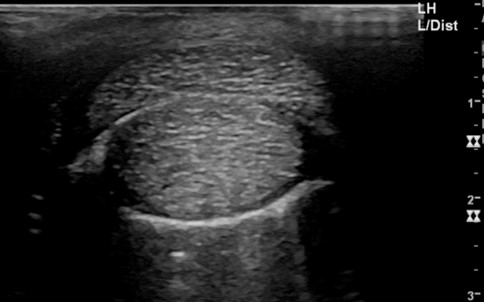

To accurately assess the depth, extension and size of acute wounds, clipping and cleaning are essential, particularly as the wound frequently extends further than anticipated before clipping (Figures 1 and 2). The use of radiographs and ultrasound can help determine involvement of, and damage to, underlying structures, demonstrate the presence of foreign bodies and give an indication of penetration of adjacent synovial structures. Gas within synovial structures may be observed as radiolucencies on radiographs (Figure 3) or hyperechogenicity on ultrasound scan, but they must be differentiated from superimposed subcutaneous gas/air within fascial planes (Figures 4 and 5).